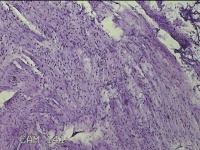

直肠息肉

性别

女

年龄

39岁

临床诊断

混合痔

一般病史

反复肛门肿物3月。

标本名称

大体所见

灰白暗红色条索状肿物5.3x2x0.8cm一个,表面糜烂,切面灰白暗红色,质软。

图2